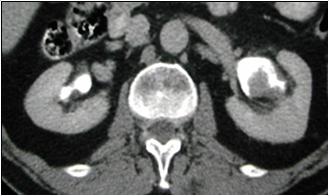

IV contrast shows tumor  in renal pelvis

Transitional cell Ca